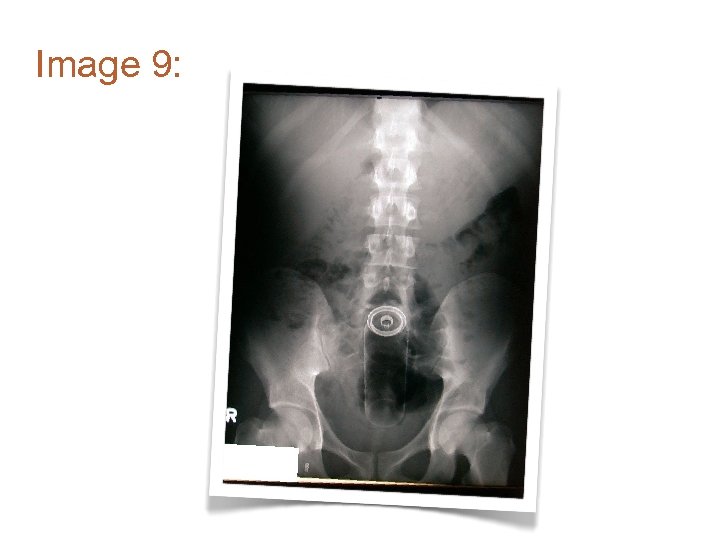

Image 9:

Image 1: • Where is the ring?